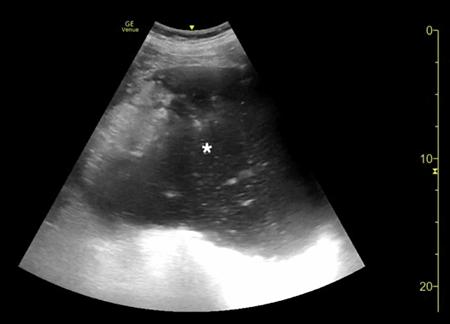

腹部床旁超声检查(POCUS)显示,胃部扩张并充满液体,高度疑似梗阻(图1,2)。

(图1 POCUS检查显示胃部膨胀充满液体[星号])

当怀疑有胃扭转时,选择初始的影像学检查非常重要,因为诊断延迟可能导致致命的并发症。CT检查高度可靠,主要有两种表现,即正常的胃窦幽门移行区和胃窦位置异常,诊断急性胃扭转的敏感性和特异性均为100%。POCUS是一种有效的非侵入性影像检查方式,主要用于床旁评估。此外,POCUS无辐射,并可根据临床情况随时进行重复检查。本例患者POCUS检查显示,胃部严重扩张,胃内容物分层,类似胃出口梗阻(GOO)的“黑白饼干”征象。POCUS还可以用来动态视察胃减压成功与否。